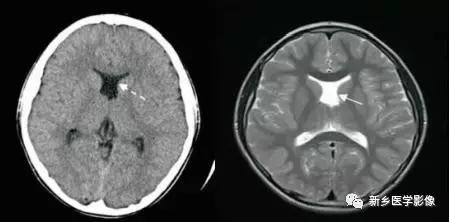

2.侧脑室神经上皮囊肿

通常位于侧脑室三角区,囊壁薄,通常显示不清由于囊内含脑脊液,所以CT及MR都表现为脑脊液信号。

4.一侧室间孔阻塞

脑脊液主要产生于脑室的脉络膜丛。当一侧室间孔阻塞时,同侧侧脑室脉络膜丛产生的脑脊液不能进入三脑室,脑脊液在侧脑室内聚积,CT和MR检查表现为一侧侧脑室扩大,扩大明显时可有中线结构向对侧移位,主要原因有室间孔附近的肿瘤、囊肿、囊虫及炎性粘连。确定一侧侧脑室扩大为室间孔阻塞所致的要点包括:一侧侧脑室扩张明显,有张力.透明隔向对侧移位;扩一大的侧脑室周围没有能够导致该侧侧脑室扩大的其他可以解释的原因。